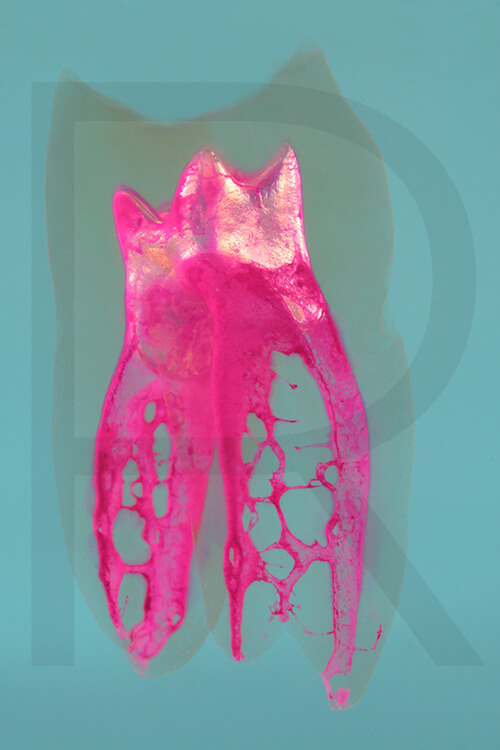

Wenn Sie Interesse an den Fotos transparenter Zahnpräparate haben, bieten wir hier die Möglichkeit einige Versionen als Acrylbilder (alle Detailinformationen zu Größe und Preis siehe obige Auswahl) zu bestellen.

Die Bilder sind nicht nur zur Praxisverschönerung geeignet sondern auch eine wertvolle Unterstützung bei der Patientenberatung vor endodontischen Behandlungen.